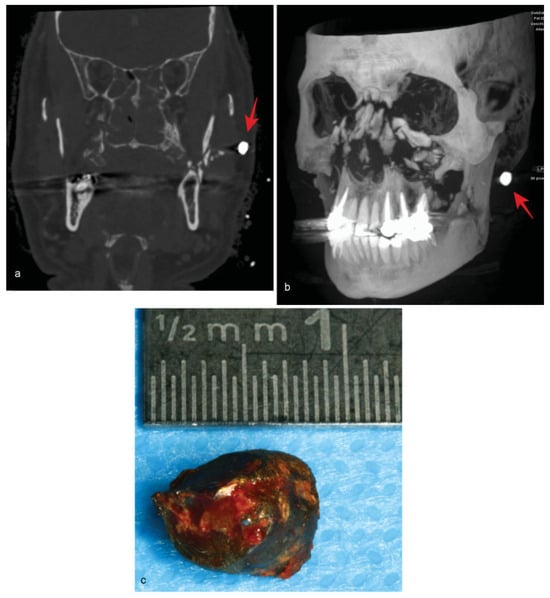

• Case 9: A critically injured 58-year-old patient with severe trauma resulting from a close explosion was transferred from a hospital in Egypt. Aside from a pneumothorax with respiratory insufficiency, the patient had also suffered multiple severe burn wounds on his hands and face. Clinically, the patient presented a complete mobile midface with an open wound on his right cheek and a pussecreting open wound under his lower right eyelid that penetrated into his nasal cavity. The MDCT imaging revealed a complex panfacial fracture with a comminuted central midface and angulus fracture of his left mandible. Furthermore, a hyperdense foreign body was visible in his left cheek (Figure 9a,b). After stabilization of the patient, surgical treatment, including thorough wound cleaning and insertion of drainage systems, temporary fracture reduction, and the removal of a metal object, was carried out (Figure 9c). The foreign body had penetrated the patient’s right cheek, exiting intraorally to also penetrate the left cheek and crush the left angulus. Due to the serious bacterial infection, as indicated by the detection of Klebsiella pneumoniae in the cerebrospinal fluid, extensive antibiotic regimes were initiated including intrathecal administration (as a treatment of last resort). However, the patient subsequently died due to multiple organ failure under progressive sepsis.

Figure 9. (a) Axial multidetector computed tomography scan showing a fractured ascending left ramus with a hyperdense structure. (b) Threedimensional reconstruction of a multidetector computed tomography scan revealing a central comminuted midfacial fracture with a hyperdense foreign object. (c) Postoperative image of the foreign object.